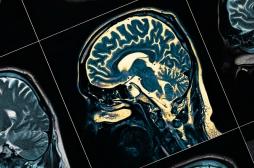

LES MALADIES

SYMPTÔMES